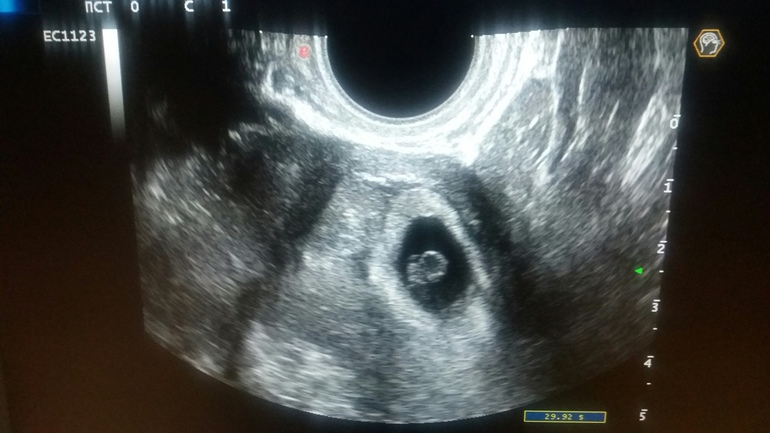

У меня сегодня 6 недель + 1 день, была Сегодня на первом узи. Слава Богу все на месте, очень переживала по поводу ВБ. Эмбриончик уже виден и сердечко бьется, слабо конечно еще видно, но видно.

Поставили только тонус, но я работаю по 12 часов на ногах, в этом наверно причина